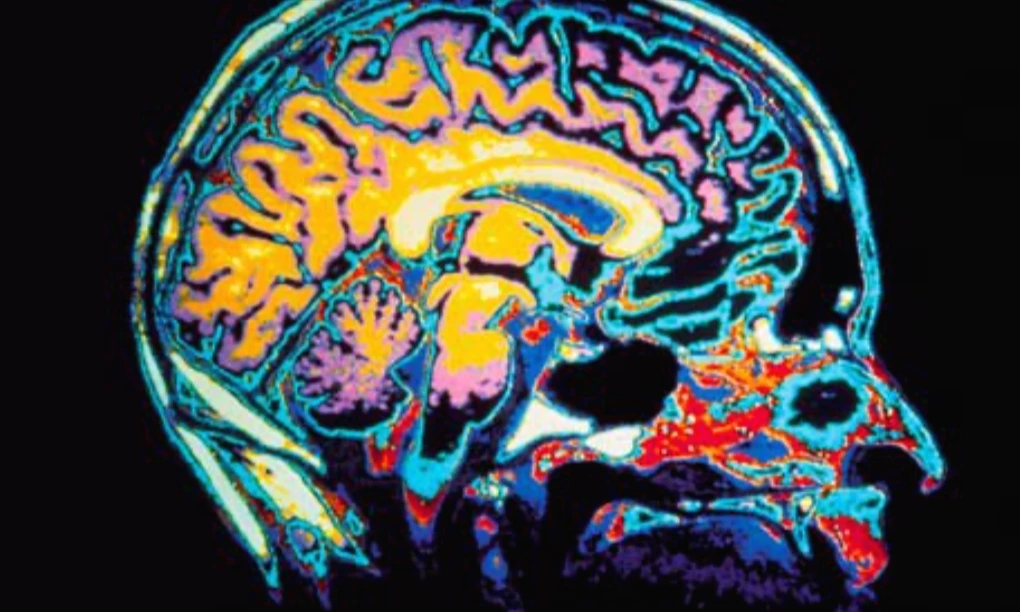

이런 자극에 대한 통제와 관련하여, 우리의 물질적인 기반인 뇌는 여러 부분들로 기능들이 나누어져 있다. 좌반구와 우반구로도 나뉘지만, 특히 더 중요하게는 중심 고랑(central sulcus)을 기준으로 앞쪽뇌(전두엽)와 뒤쪽뇌(두정엽, 측두엽, 후두엽)로 나눌 수 있다.

중앙면(midline)에서 본 인간의 뇌 이미지

뒤쪽뇌는 외부에서 들어오는 자극들을 받아들이는 부분인데, 시각적 정보는 뇌의 뒤쪽인 후두엽(occipital lobe)에서 처리되고 청각적 정보는 측두엽(temporal lobe)의 후방 3분의 1에 위치한 영역인 베르니케 영역(Wernicke’s area) 그리고 온몸의 촉각 정보들을 받아들이는 감각피질(sensory cortex)이 뇌의 뒤쪽에 위치해 있다. 또한 감정 자극을 처리하고 감정적 기억들을 담당하는 편도체(amygdala), 인지적인 기억을 처리하는 해마(hippocampus) 등도 뇌의 뒤쪽에 위치해 있다.

스크린샷 2019-11-17 오후 1.13.06.png 첫번째 사진을 기준으로 앞쪽의 청보라색은 전두엽, 위 가운데의 주황색은 두정엽, 뒤쪽 살색은 후두엽, 연녹색은 측두엽. 마지막 사진은 중심이랑(central sulcus) 위치.

반면, 앞쪽뇌인 전두엽은 외부에서 들어온 자극을 능동적으로 통제하고 조절하는 역할을 한다. 뒤쪽에서 처리된 외부자극의 정보들을 앞쪽뇌는 판단하고 반응하는 역할을 하는데, 외부에서 부정적인 정보(예를 들어, 화를 내는 상대 또는 듣기 싫은 소리나 잔인한 장면)가 들어올 때 전두엽은 이에 대한 반응(화를 내거나 귀를 막거나 눈을 감는 등의 행동)을 하기도 한다. 또한 말하기 영역인 브로카 영역(Broca's area)도 전두엽 측면에 있다. 따라서 앞쪽뇌는 우리가 능동적으로 반응하는 영역이다.